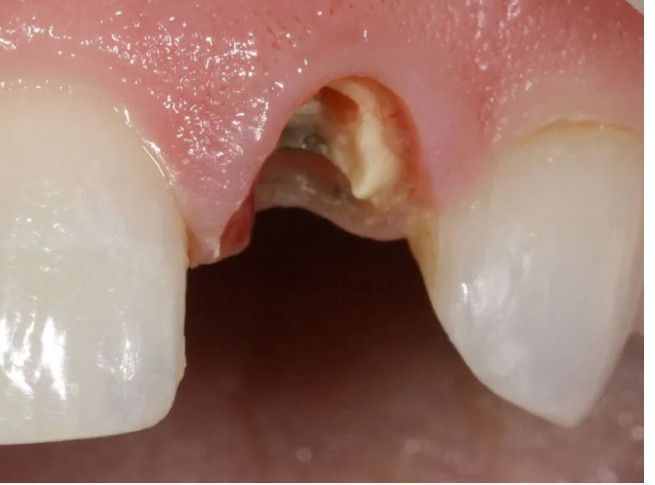

Broken down root

A fractured root is a break in the hard outer layer of a tooth that extends into the root. This can be a serious condition, as it can lead to pain, infection, and tooth loss.